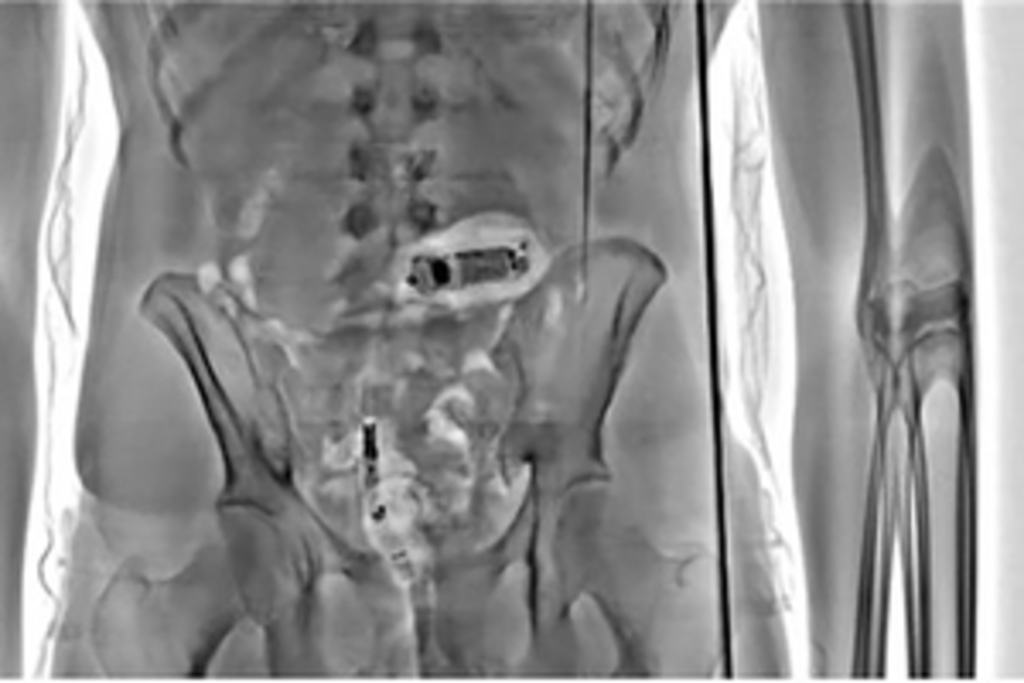

ADVANCED X-RAY body scanners have prevented over 1,376 illegal items, including drugs, weapons and mobile phones, from entering the prison estate in the four-month period since they were installed. The innovative equipment being rolled out across England and Wales is part of the Government’s bold £100 million package designed to boost security in prisons and crack down on criminality behind bars.

Developed specifically for the Prison Service, the 28 scanners allow members of staff to see instantly whether individuals are attempting to smuggle illegal contraband items internally. They’ve picked up Spice, morphine tablets, mobile phones, SIM cards, phone chargers and tobacco. These illegal items would have been destined for the prison wings, in turn fuelling the illicit economy and potential violence.